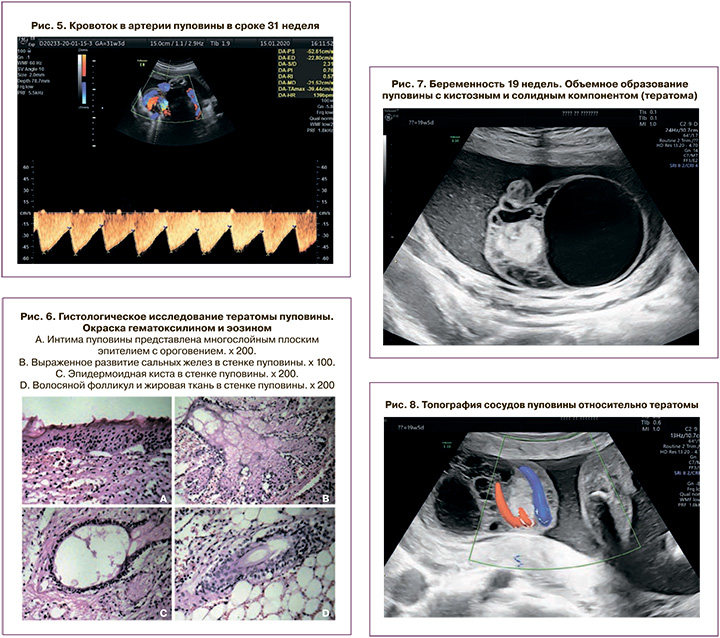

Беременная М., 26 лет. Первая беременность закончилась прерыванием в 21 неделю по поводу множественных врожденных пороков развития плода; вторая беременность – срочными родами здоровым ребенком. Данная беременность третья. Исследование проведено в 19–20 недель. Размеры плода соответствовали сроку беременности. Аномалий плода не выявлено. Определялось образование пуповины: свободный участок пуповины от корня до образования – 60 мм, от образования до пупочного кольца – 40 мм.

На протяжении пуповины определялось кистозное образование общими размерами 77×50×59 мм, объем – 118 cм3. В структуре образования – киста 47×42 мм, тонкостенная, анэхогенная, ячеистое образование по типу отека вартонова студня размером 46×31 мм и гиперэхогенный фрагмент, возможно тератома, размером 32×18 мм (рис. 7). Вена пуповины проходила по периферии гиперэхогенного фрагмента образования, без компрессии. Одна артерия пуповины проходила между тератомой и кистой, риск компрессии невысокий. Вторая артерия пуповины определялась в толще гиперэхогенного солидного включения, существовал риск компрессии артерии (рис. 8). Заключение: беременность 19 недель 5 дней. Объемное образование пуповины (тератома). Относительная короткость пуповины.

По решению акушерского консилиума рекомендованы ультразвуковая фетометрия и допплерометрия каждого сосуда пуповины через 2 недели. Следует заметить, что ко времени консультирования данной пациентки в МОНИИАГ специалисты ультразвуковой диагностики были информированы о перинатальном исходе и причине антенатальной гибели плода у пациентки, представленной в клиническом наблюдении 1, поэтому программа наблюдения составлена с учетом индивидуальных факторов риска. Несмотря на рекомендации, пациентка на осмотр не явилась.

Повторно осмотрена в 25 недель гестации. Фетометрические показатели соответствовали менее 3 перцентиля, предполагаемая масса плода 600 г (менее 3 перцентиля), что соответствовало ранней задержке роста плода (ЗРП). Общий объем образования пуповины составил 300 см3. Допплерометрия артерии пуповины: систоло-диастолическое отношение (СДО) – 4,8, ПИ – 1,39 (соответствует 94 перцентилю). Продолжено амбулаторное наблюдение.

При гестационном сроке 26 недель 6 дней размеры плода соответствовали 24 неделям беременности; предполагаемая масса 660 г (менее 1 перцентиля) Диаметр свободного участка пуповины 12–13 мм. На протяжении пуповины определялось кистозное образование общими размерами 115×79×85 мм, объем – 420 cм3 (рис. 9). В структуре образования – киста 78×58×80 мм, объем – 194 cм3, тонкостенная, анэхогенная; ячеистое образование по типу отека вартонова студня размером 46×31 мм и гиперэхогенный фрагмент, возможно, тератома, размерами 33×26×29 мм, объем – 14 cм3. Топография сосудов пуповины относительно тератомы прежняя. Допплерография: частота сердечных сокращений – 133 в 1 минуту. Артерия пуповины в толще солидного образования – тератомы: СДО – 7,4, ПИ – 1,55 (более 95 перцентилей) с эпизодами нулевого кровотока в диастолу (рис. 10). Артерия пуповины, проходящая по краю образования: СДО – 3,22, ПИ – 1,11 (50 перцентилей). Артерии пуповины (на свободном участке): СДО – 4,0, ПИ – 1,27 (менее 95 перцентилей). Средняя мозговая артерия: ПИ – 1,54. Заключение: беременность 26–27 недель. Головное предлежание. Ранняя ЗРП. Объемное образование пуповины (вероятнее – кистозная тератома). Гемодинамические нарушения в артериях пуповины с критическими значениями диастолического кровотока в одной из артерий.

С учетом высокого риска антенатальной гибели плода пациентка направлена в перинатальный центр, имеющий условия и большой опыт в выхаживании недоношенных новорожденных с экстремально низкой массой при рождении. При гестационном сроке 29–30 недель отмечено прекращение шевелений плода, при допплерометрии – нулевой диастолический компонент в обеих артериях пуповины, в связи с чем экстренно родоразрешена путем кесарева сечения. При рождении масса новорожденной составила 880 г (менее 3 перцентиля). В настоящее время ребенок находится на 2 этапе выхаживания, самостоятельно дышит, адекватно прибавляет вес.